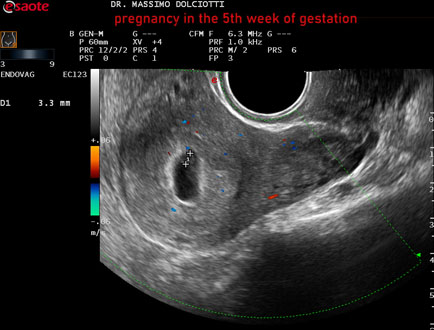

Data inserimento: 12/12/2025

Ecografia del: 31/11/2025

Strumento: Esaote MyLab Eight

Sonda: Convex Multifrequenza 1-8 MHz ed Endocavitaria Multifrequenza 3-9 MHz

Età Paziente: F 28 anni

Motivazione dell'esame: amenorrea e BETAHCG POSITIVO 17 mila.

Commento all'esame: le immagini ed il video documentano la camera gestazionale delle dimensioni di 13 x 7 mm e presenza di sacco vitellino delle dimensioni di 3,3 mm.

Conclusioni: gravidanza alla quinta settimana di gestazione (pregnancy in the 5th week of gestation).